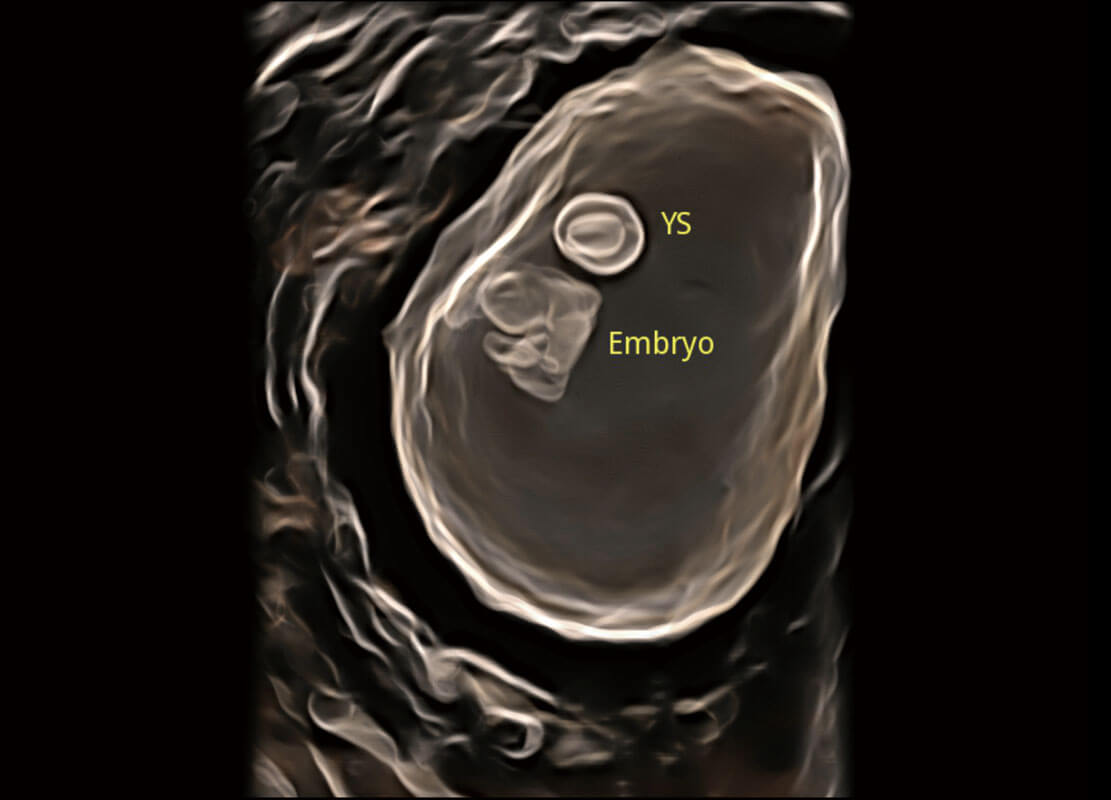

早孕筛查

• 高分辨率容积成像-早孕胎儿

• 光影成像-孕囊